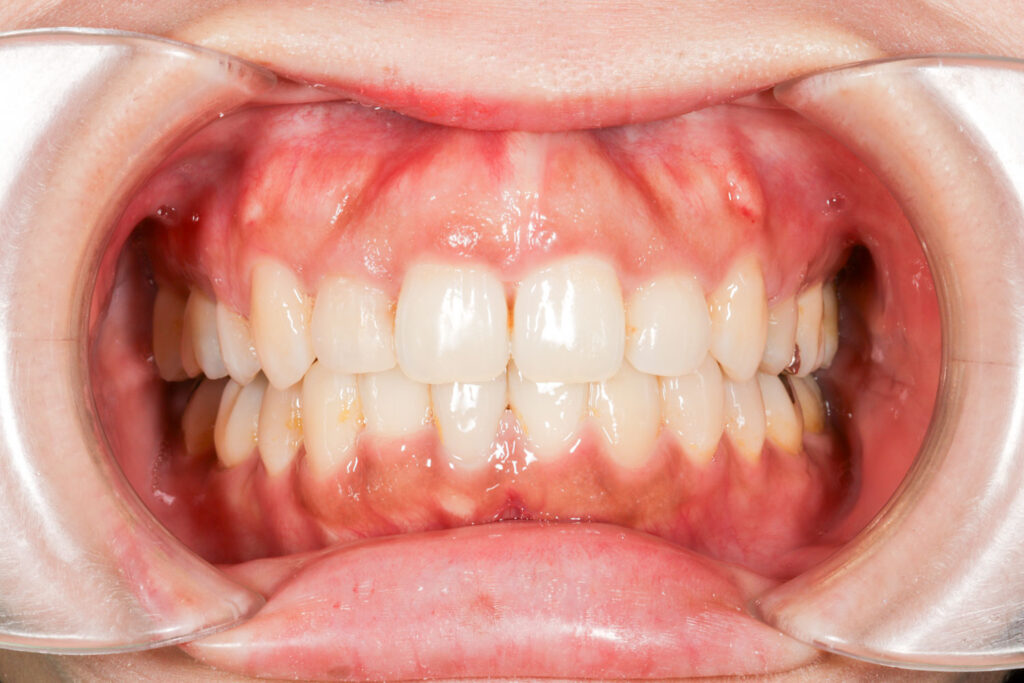

Before

After

年齢 20代

治療装置 表側矯正装置(ホワイトコース)

治療内容 上下左右4本抜歯

治療期間 2年10ヶ月

リスク 歯の移動に伴う痛み、歯肉退縮、歯根吸収、歯肉炎、虫歯

主訴 ガタガタと前歯で噛めない

症状 開咬と叢生

治療回数 36回程度

総額費用 105万円程度